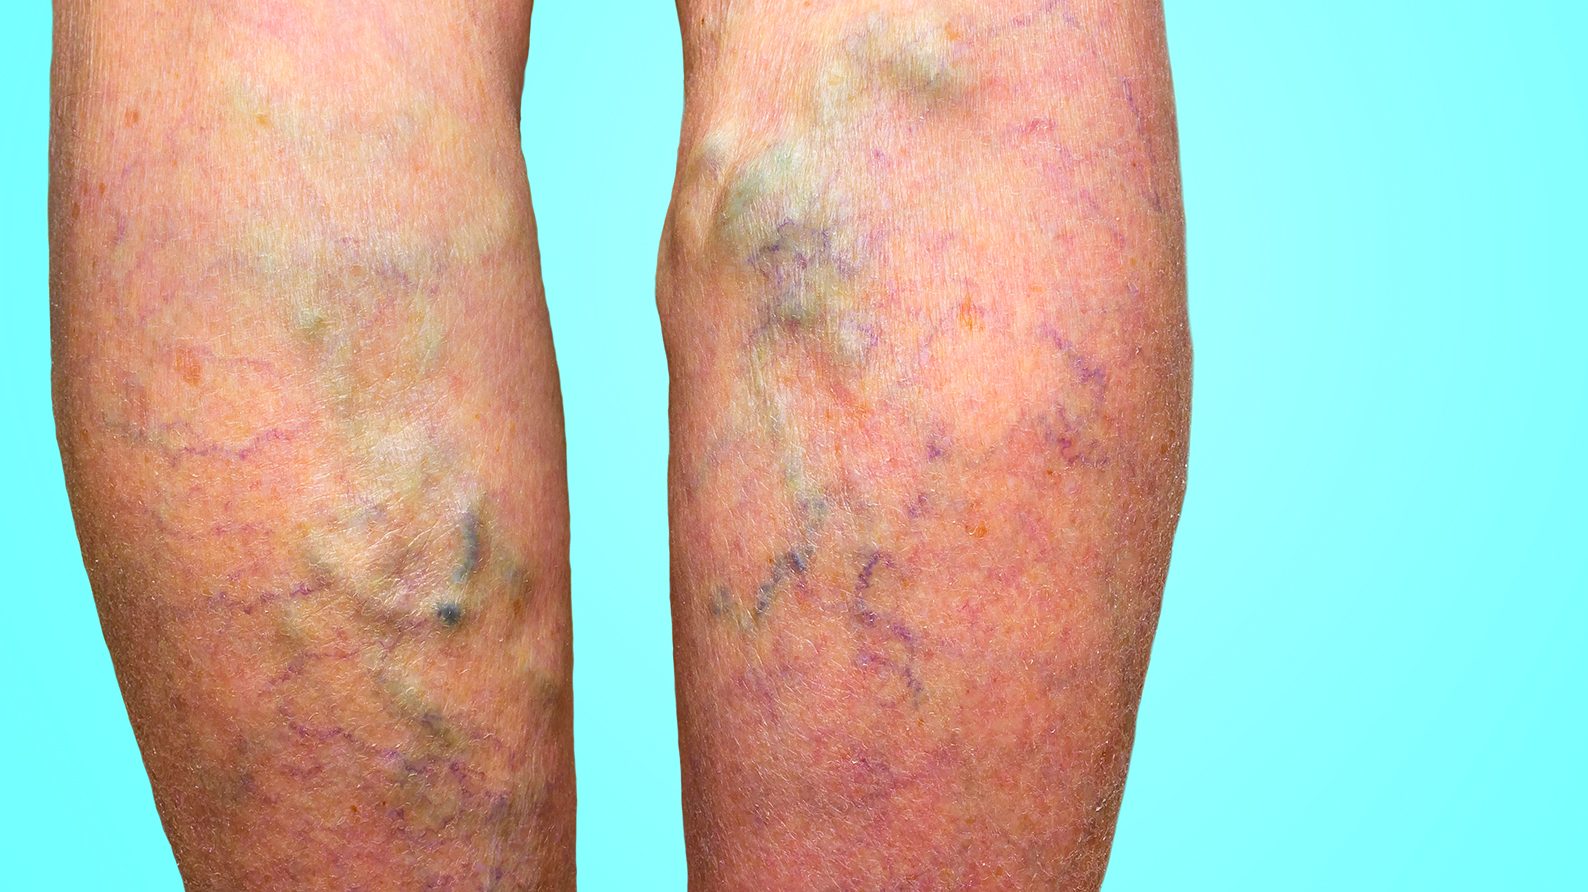

Les varices sont des veines irréversiblement endommagées; le sang peine à retourner vers le cœur et s’accumule dans celles-ci, ce qui entraîne leur dilatation.

Ainsi, outre un aspect inesthétique, elles peuvent provoquer un durcissement ou une pigmentation permanente de la peau, des ulcères veineux et, parfois, un caillot sanguin.

On estime que de 15 à 30% de la population a des varices et que les femmes sont deux ou trois fois plus touchées que les hommes.